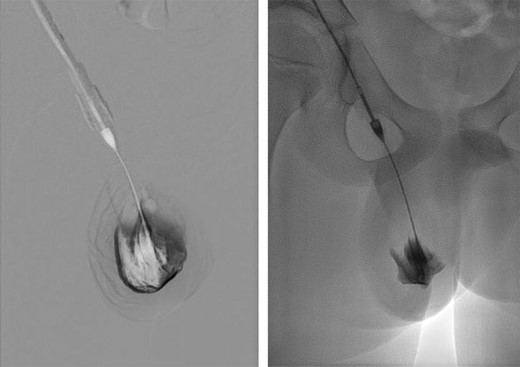

Six weeks post-operatively the hydrocele persisted. Time was allowed for the hydrocele to resolve but during the following 3 months the hydrocele continued to enlarge and cause discomfort. The case was discussed with the interventional radiology team and treatment by aspiration and sclerosis (Fig. 3) was offered, for both the scrotal sac and a residual intra-abdominal component, if present. At the time of treatment, the lesion was shown to be confined to the scrotum. Following two treatments with sodium tetradecyl sulphate foam, 2 months apart, resolution was confirmed on both clinical and USS examination. The testes were normal upon final USS 3 months after completion of sclerotherapy.